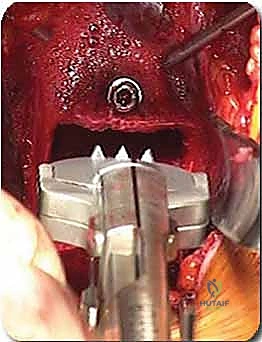

تثبيت مفصل إبهام القدم الكبير: الحل الجراحي المتقدم لإبهام القدم المتصلب مع الأستاذ الدكتور محمد هطيف

تعرف على عملية تثبيت مفصل إبهام القدم الكبير (MTP) لعلاج إبهام القدم المتصلب المتقدم. يقدم الأستاذ الدكتور محمد هطيف في صنعاء أحدث التقنيات…